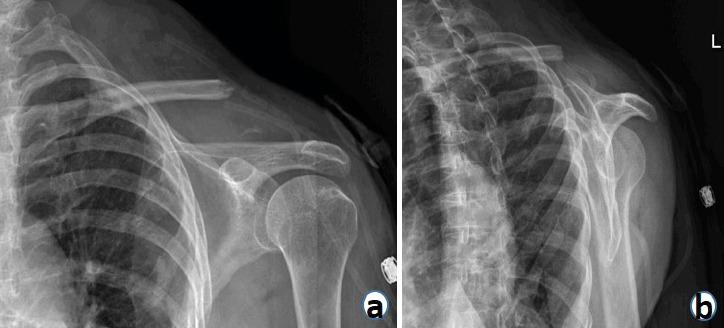

We present a 65-year-old female with no reported medical history, who presented to our institution with left clavicular pain and wound drainage 8 days after she was struck by a motor vehicle in her home country of Guyana. She was found to have a missed open clavicle fracture with an associated severe infection. She was subsequently treated with irrigation, debridement, and distal clavicle excision.

A 65-Year-Old Female with Missed Open Clavicle Fracture and Subsequent Fracture-Related Infection, Treated with Distal Clavicle Resection.